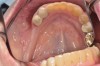

(1. AND 2.) Removable appliance.

Figure 1

Figure 2